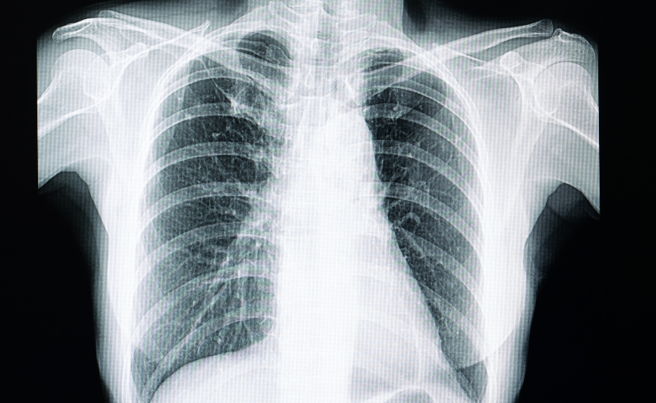

苏一峰昨在脸书上分享,一名60多岁的女患者去年检查出1颗肺结节,之后一直定期检查追踪,没想到今年做电脑断层却发现,本来只有1颗肺结节竟变成「满天星」,有多达10颗肺结节,让医师看了直摇头,表示可能需要开刀处置。

苏一峰指出,过量消毒液挥发具有「肺呼吸道毒性」,恐让肺部发炎,出现「满天星」的肺结节,而满天星的肺结节找到原因就可以处理,他马上卫教病人正确的消毒观念,并给予适当的消炎药物。